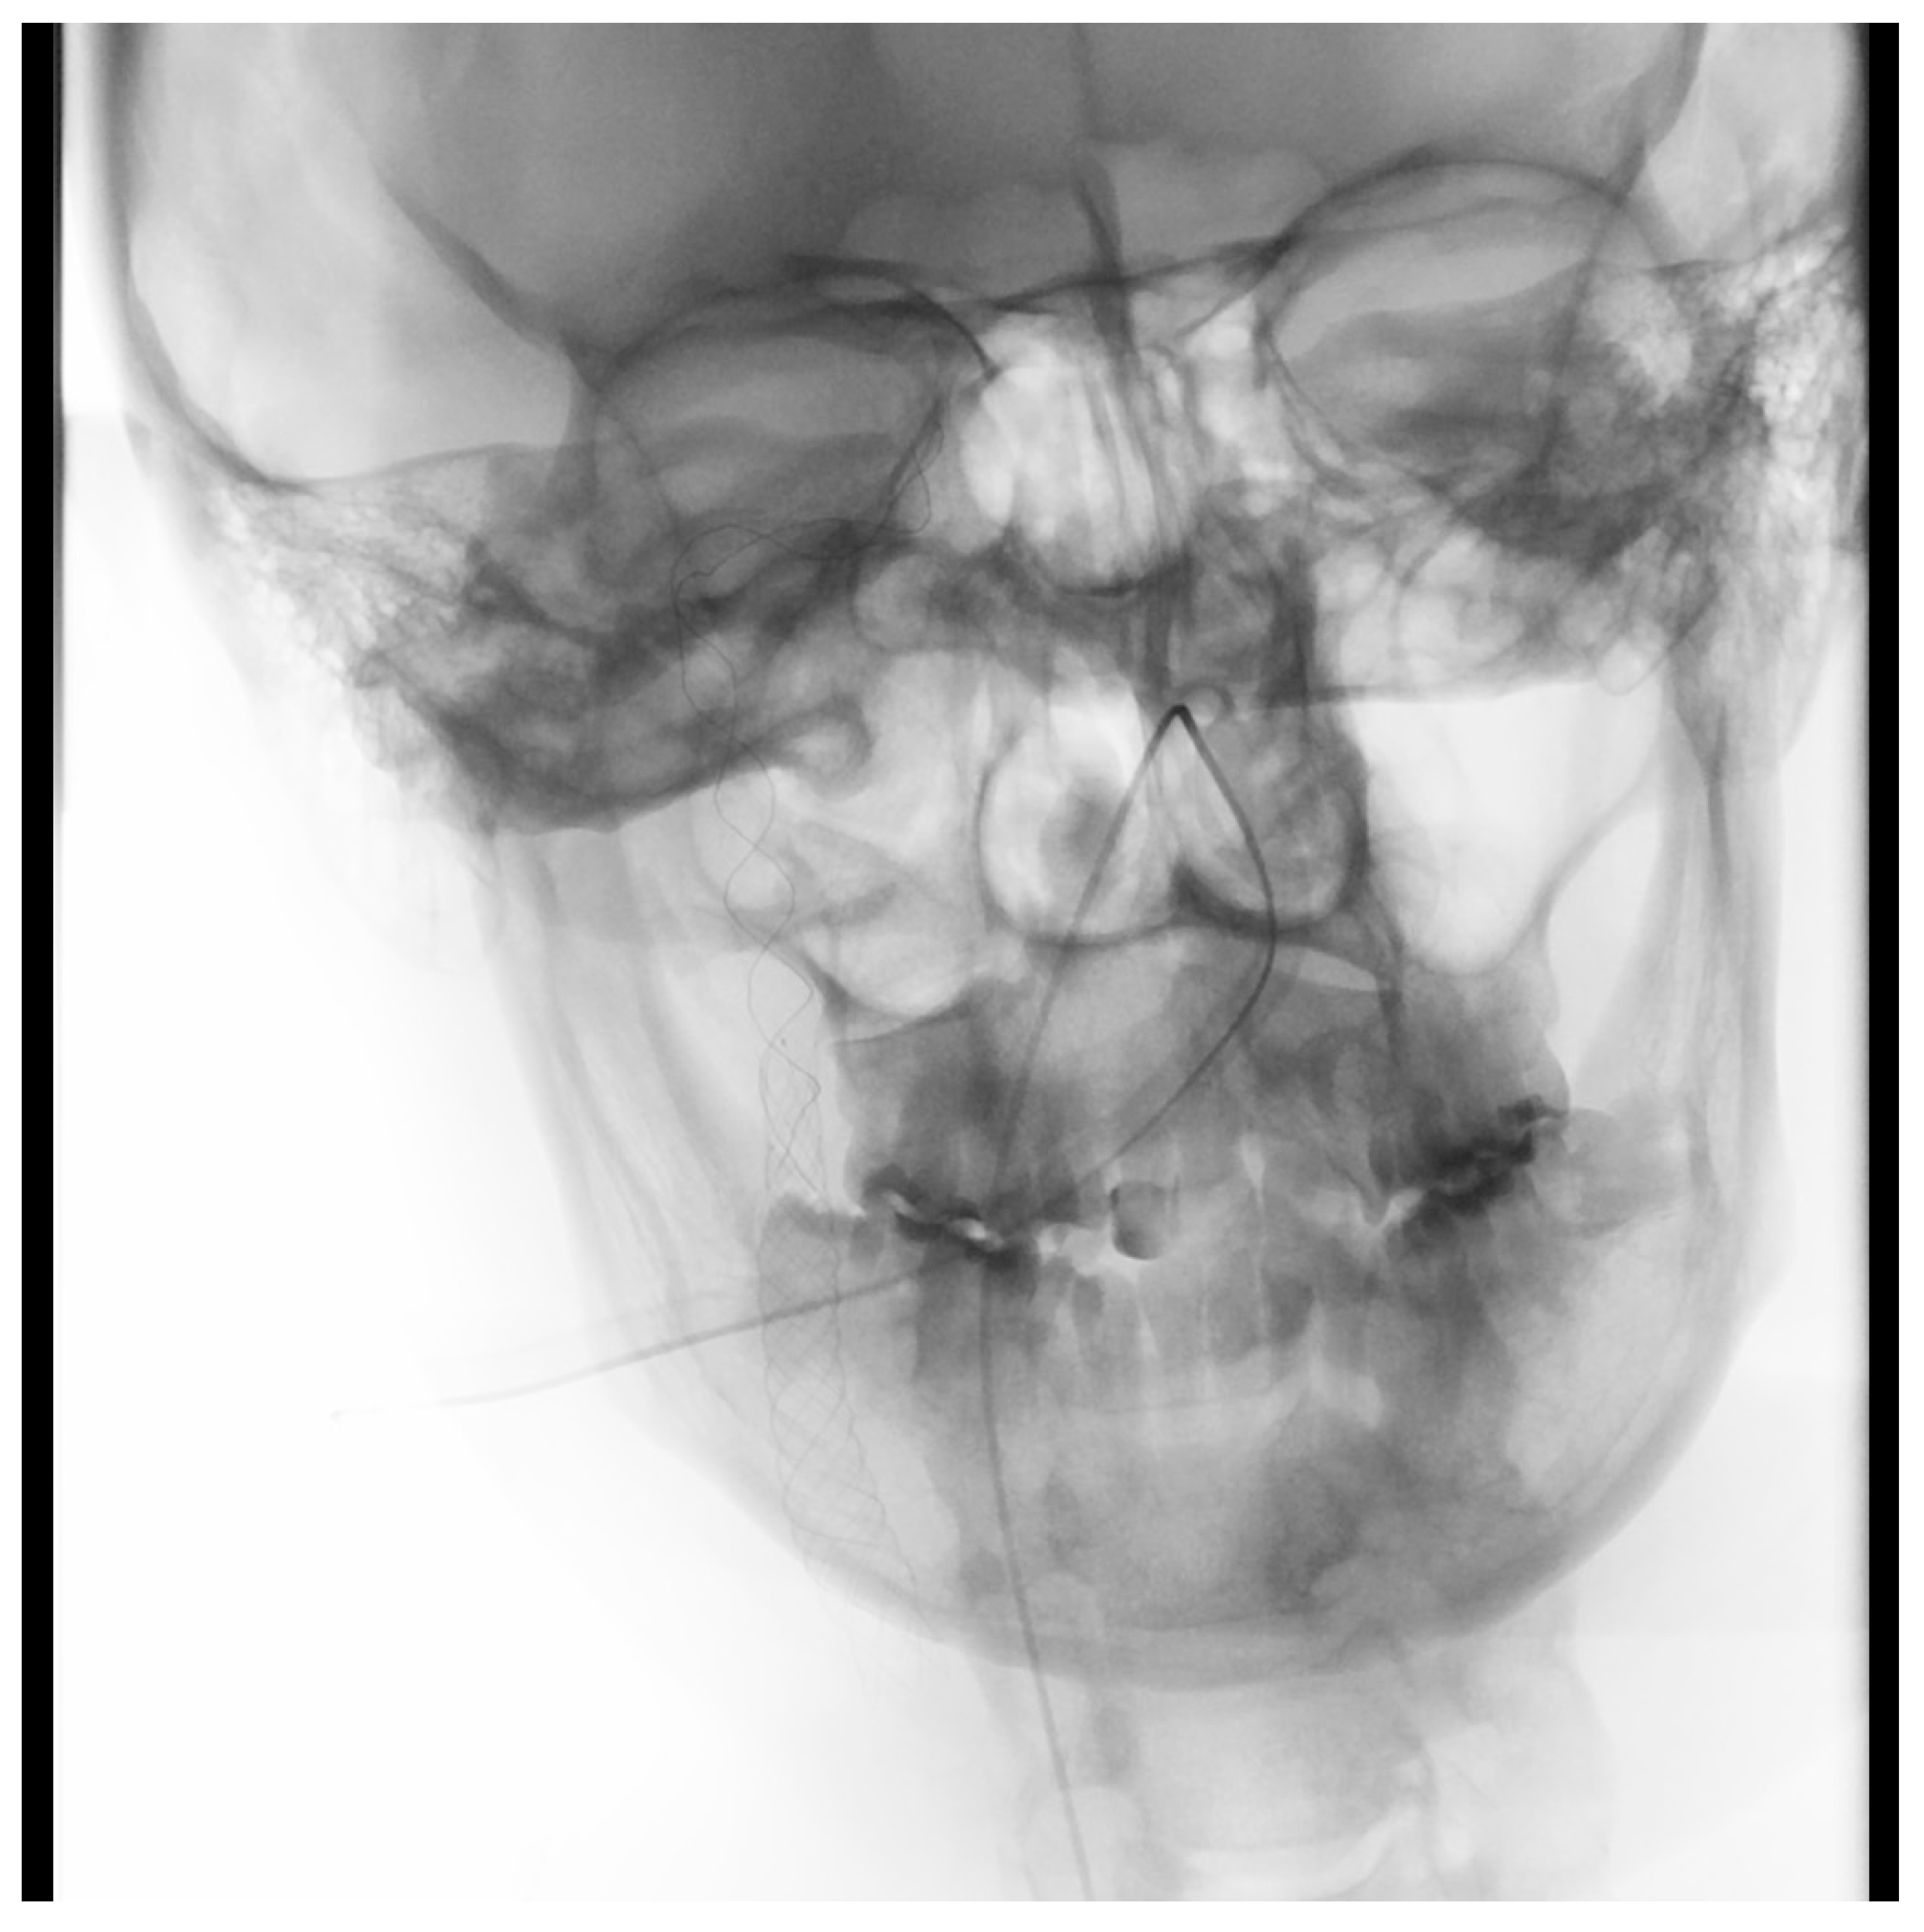

2. Case Presentation